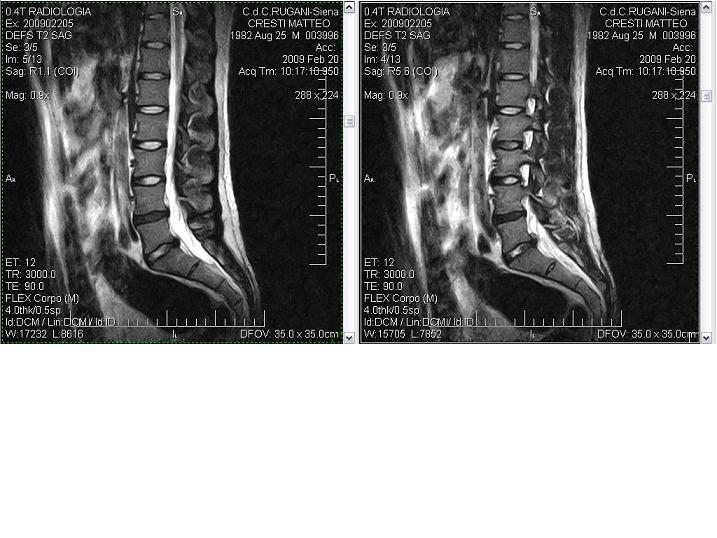

RM Rachide Lombosacrale

Attenuazione della fisiologica lordosi lombare, per rigidità.

Modesta protusione anulare del disco L4-L5, che presenta segni di disidratazione nel suo nucleo polposo; la protusione lambisce le tasche radicolari, senza tuttavia effetti compressivi.

Segni di discopatia degenerativa anche a carico del disco L5-S1, caratterizzato dalla presenza di una ernia postero-laterale destra, con una minima quantità di materiale discale espulso verso l'alto.

Il canale midollare mostra ampiezza nei limiti della norma.

Non si rilevano alterazioni di segnale a carico del cono midollare nè della cauda.